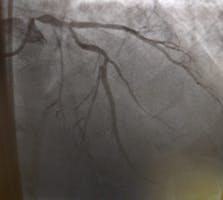

Recuperarea după coronarografie

Angiografia coronariană sau coronarografia este o procedură medicală prin care se poate diagnostica o boală coronariană, prin identificarea precisă a locurilor în care arterele coronare sunt îngustate.

Despre Coronarografie - ce este și cât durează o astfel de procedură?

Coronarografie : procedură medicală unică ce permite verificarea precisă a condițiilor de sănătate a arterelor care alimentează inima. Prin intermediul acesteia, este posibilă depistarea îngustărilor vaselor de sânge, care poartă numele de stenoze.